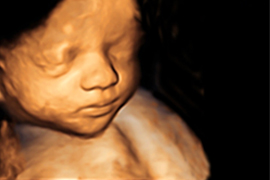

3D/4D-Ultraschall

3D-Ultraschall

Eine 3D- oder im Live-Bild 4D-Aufnahme lässt die Herzen vieler Eltern höher schlagen – zum ersten Mal können Sie sich ein lebensnahes Bild oder eine „Live-Aufnahme“ von ihrem Kind ansehen! Die Ultraschallbedingungen werden aber nicht von jedem Kind perfekte Porträts ermöglichen: Es muss ausreichend Fruchtwasser vorhanden sein, es dürfen weder Hände noch Nabelschnur vor dem Gesicht sein – und Ihr Kind muss uns ansehen!

Es gibt aber auch eine Reihe von medizinischen Gründen für die Anwendung von 3D-/4D-Ultraschall.

Im 3D- oder 4D-Ultraschall wird die Ebene durch das Ultraschallgerät rekonstruiert, die durch die einfache 2D-Sonographie nicht darstellbar ist. Dies kann bei ungünstigen Kindslagen notwendig sein. Am Kopf oder Herz des Kindes ist der 3D oder 4D-Ultraschall oft hilfreich um die kleinsten, verborgenen Strukturen darzustellen. Aber auch eine Aufsicht auf Gesicht und Körper kann notwendige Informationen liefern.